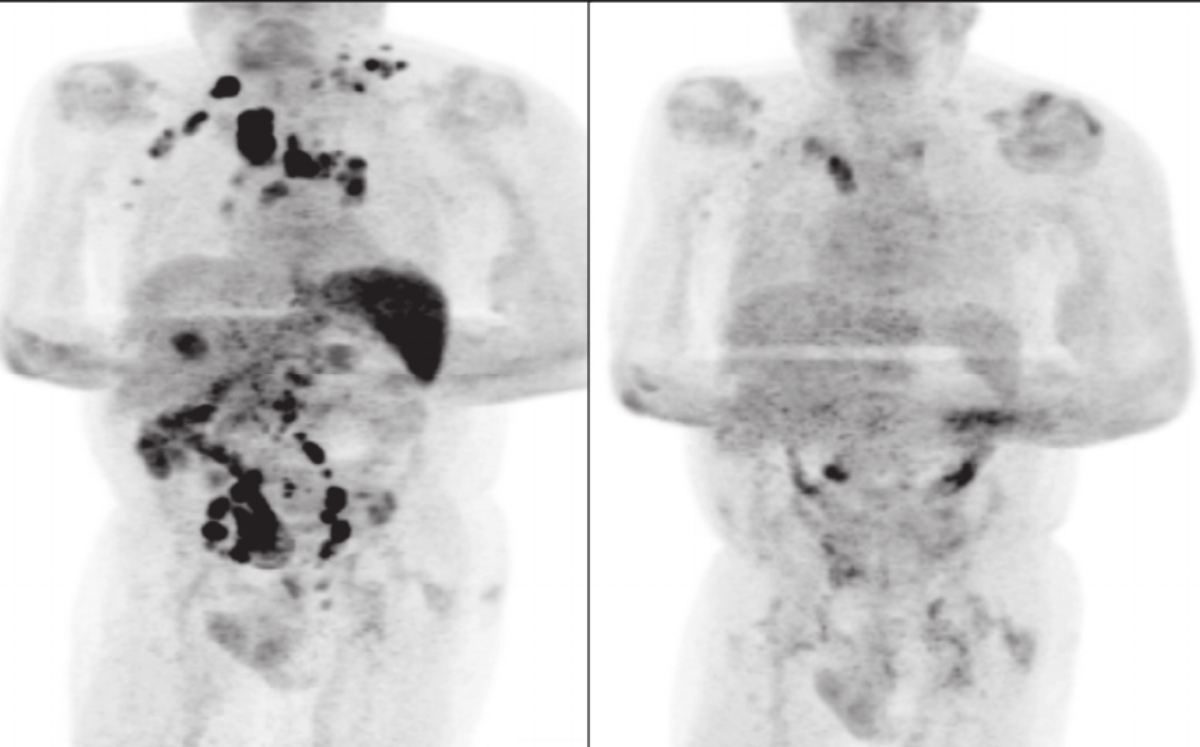

En el estudio, relatan que "la tomografía (...) computarizada reveló una enfermedad ávida en estadio III", es decir, una de las etapas más avanzadas de este tipo de cáncer.

La sorpresa se la llevaron cuatro meses después, cuando "la linfadenopatía palpable se había reducido" como se observa en las fotos. Estudios adicionales revelaron "una resolución generalizada de la linfadenopatía y una reducción de la captación metabólica en todas partes".